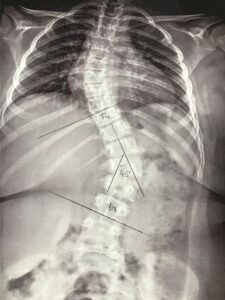

• COLETES

• COLETES ORTOPÉDICOS

2. COLETES PARA CORREÇÃO OU ESTABILIZAÇÃO DA COLUNA VERTEBRAL EM ITAJAÍ E REGIÃO